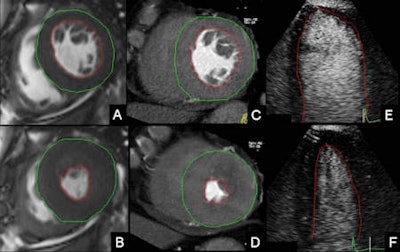

Dual-source CT is as accurate as MRI, and better than echo, for evaluating the left ventriculum (LV) years after patients receive transplanted hearts, according to a joint Spanish and Italian study in the European Journal of Radiology that compared dual-source CT (DSCT) and echocardiography with cardiac MRI (CMR).

DSCT was closely tied to CMR measurements, the study team found, but echocardiography was too imprecise to compete with either advanced modality.

The results showed no statistical difference between left ventricular volumes in DSCT and CMR. The mean end-diastolic volume (EDV), end-systolic volume (ESV), and stroke volume (SV) at DSCT were all very similar to the CMR assessments (p > 0.5), Arraiza and colleagues reported.

The mean ejection fraction didn't differ significantly between DSCT and CMR even when the difference was very close to statistical significance (p = 0.051), and there was good correlation between DSCT and CMR for left ventricular measurements (r ≥ 0.77; p < 0.0001).

However, left ventricular measurements were statistically different when echocardiography was compared with DSCT and CMR, they said, with echo showing a lower mean EDV (86.7 ± 24.2 mL), ESV (29.4 ± 18.7), SV 57.5 ± 14.1 mL), and a higher mean ejection fraction (EF) than both DSCT and CMR (p <0.05).

"The main finding of the present study is that DSCT allows estimating left ventricular volumes and ejection fraction similarly to CMR in orthotopic heart transplant recipients," Arraiza and colleagues wrote. "Evaluation of these parameters with [contrast-enhanced echocardiography] results in significant underestimation of left ventricular volumes and overestimation of left ventricular ejection fraction."

Agreement and reliability for left ventricular measurements were notably higher between cross-sectional imaging techniques compared with the agreement observed between echo, and either DSCT or CMR.